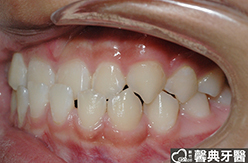

上、下顎前突,俗稱暴牙,由於上下前牙向前暴出,在外觀上容易產生牙齒外露的現象,雙唇較難自然閉合,嘴唇看也來也會比較厚。

患者︰趙同學,20多歲,學生。

主訴︰齒列不正,暴牙,不好看。

治療計劃︰上下顎齒列平整、後縮,重建正常咬合關係。